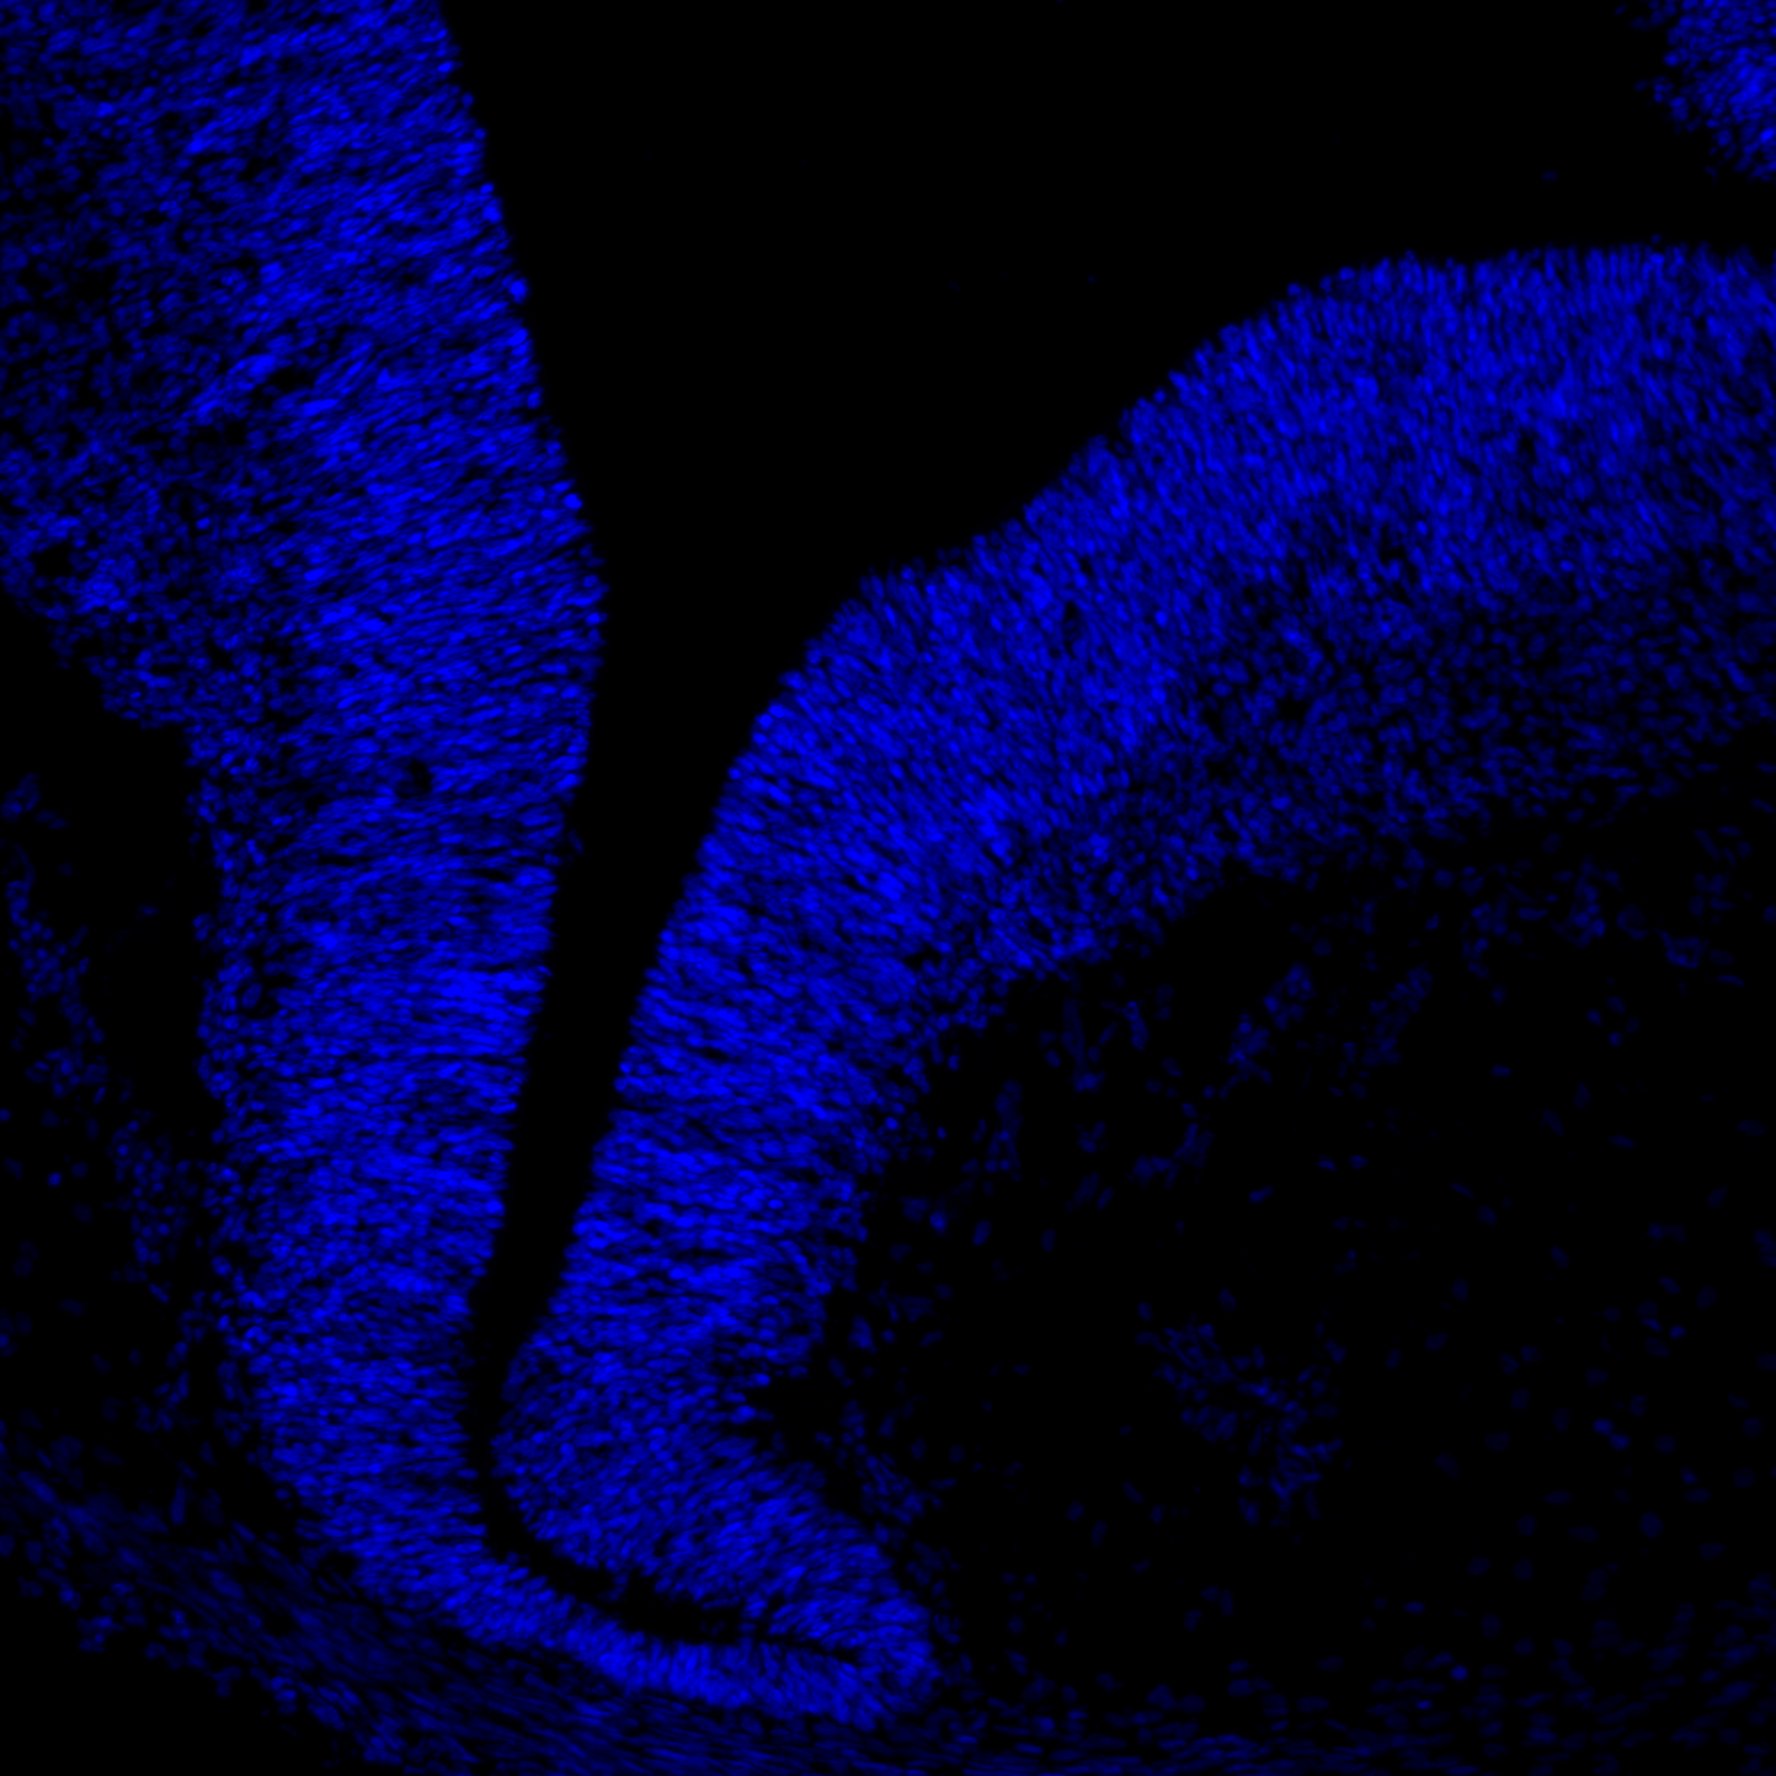

6PCW

DAPI

6PCW human midbrain